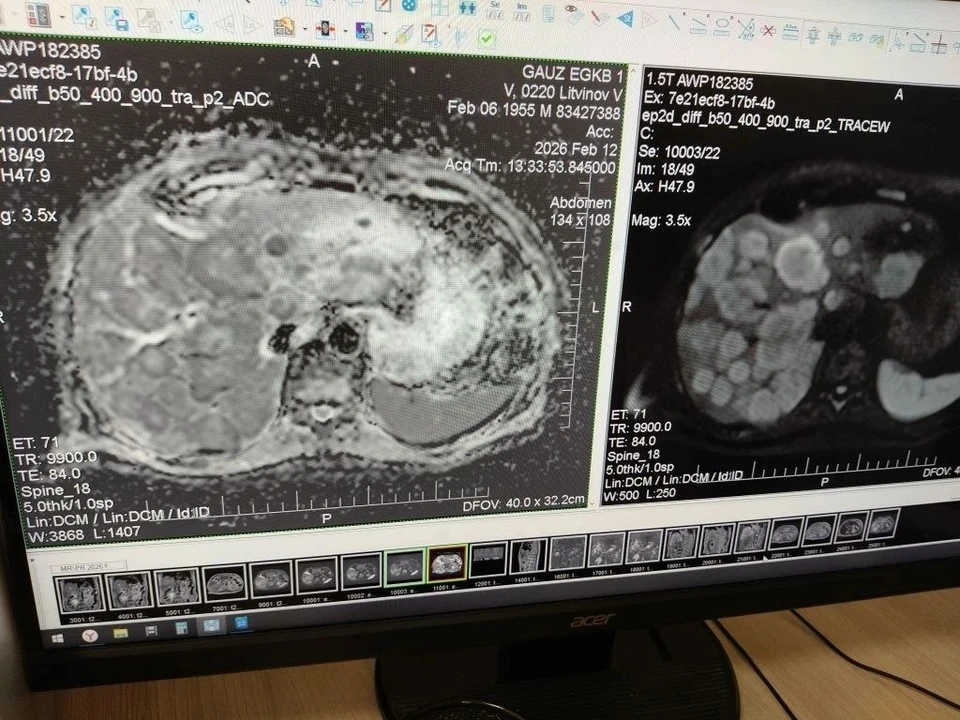

Фото: ГАУЗ "Энгельсская городская клиническая больница №1"

В Энгельсскую городскую клиническую больницу № 1 обратился 71-летний пациент с жалобами на тошноту, слабость и дискомфорт в правом подреберье. Мужчину госпитализировали в гастроэнтерологическое отделение. МРТ выявило множественные гигантские образования печени, по признакам похожие на вторичное поражение. В анамнезе пациента — оперативное лечение по поводу заболевания мочевого пузыря.

После консилиума с врачами-урологами пенсионера направили на МРТ органов малого таза. Исследование показало образования стенки мочевого пузыря с прорастанием в его полость. Медики оперативно диагностировали заболевание и приняли решение о направлении пациента на специализированное лечение.